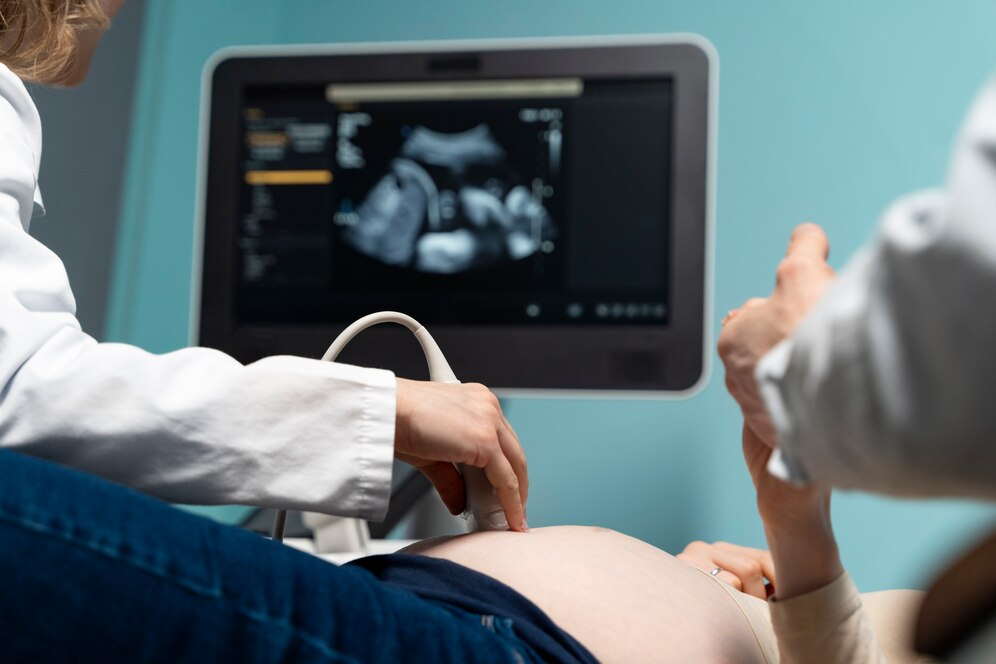

5. Siêu âm

Siêu âm được sử dụng để chụp hình ảnh từ bên trong cơ thể bằng cách sử dụng sóng âm thanh tần số cao ở các mô mềm như nội tạng và mạch máu. Đối với các trường hợp cần hạn chế tiếp xúc với chất phóng xạ, thì siêu âm là lựa chọn tốt để kiểm tra, ví dụ phụ nữ mang thai.

Chuẩn bị trước siêu âm sẽ phụ thuộc bộ phận nào cần siêu âm. Đối siêu âm ổ bụng, bệnh nhân phải nhịn ăn, nhưng được uống nước. Người bệnh sẽ nằm xuống bàn khám và bác sĩ sẽ bôi một loại gel đặc biệt lên da và sau đó, sử dụng đầu dò của máy siêu âm để phát sóng âm thanh tần số cao vào trong cơ thể khi đầu dò di chuyển trên da. Những sóng âm thanh này sẽ tạo ra hình ảnh về những gì đang xảy ra bên trong cơ thể và hiển thị trên màn hình điện tử.